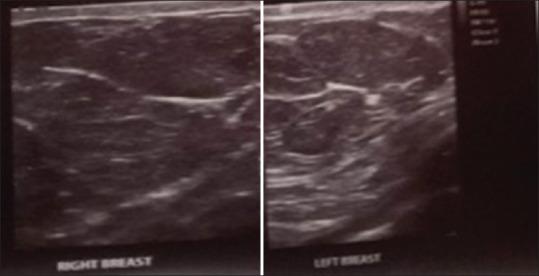

A 2-year retrospective review of breast sonograms of 25 consecutively presenting children and adolescents (3 males and 22 females) who had palpable breast masses. Ultrasound scans were performed with a Mindray Machine DC-8 using the linear transducer at 7.5-12 MHz transducer frequency. Histopathological confirmation of the solid masses was also obtained. The statistical analysis of the data collected was done using the SPSS software version 20 (SPSS Inc., Chicago, IL, USA).

The patients were between 40 days and 19 years old (mean 14.8 years and standard deviation 4.1). The ultrasonographic findings were those of infections, benign tumoral lesions and pubertal endocrine changes. Overall, fibroadenoma was the most common mass, seen in 14 (56%) of the patients. Other findings were simple cysts, non-puerperal and puerperal mastitis, juvenile papillomatosis and normal glandular pubertal breast tissue. The three male patients had gynaecomstia, pseudogynaecomastia and cystic lymphangioma of the chest wall presenting as unilateral breast masses, respectively. There was no malignancy recorded in any of the patients.